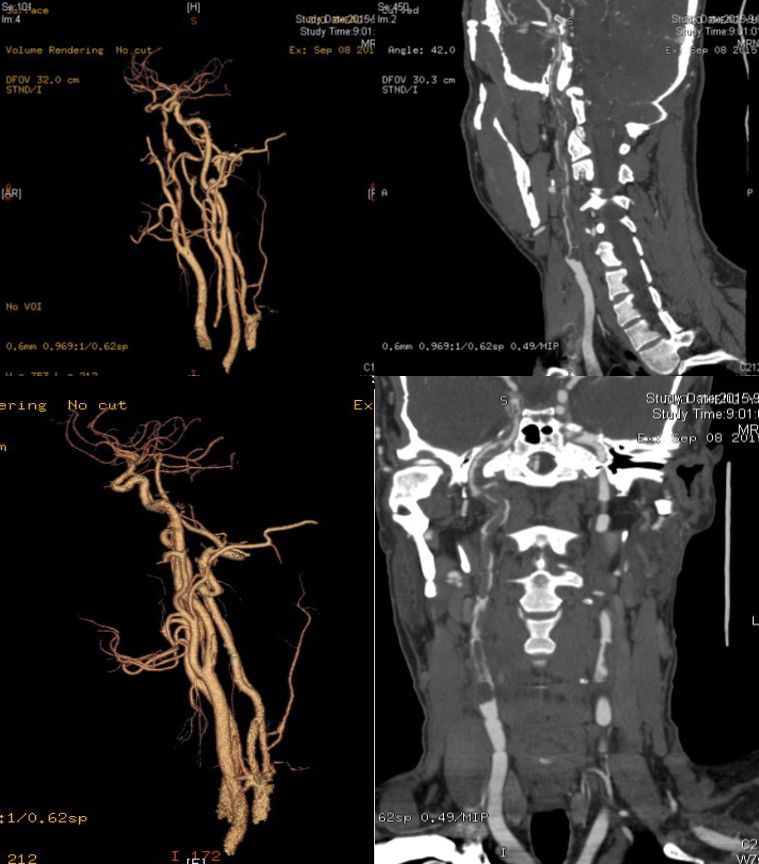

女,70岁,反复胸闷痛5年,头痛1周。

答案:大脑凸面蛛网膜下腔出血(cSAH)。其病因多样,如果年龄>60岁,临床反复发作性短暂性神经功能缺损症状,考虑脑动脉狭窄或闭塞(包括烟雾病)和CAA。如果临床<60岁,病程中伴有头痛,考虑静脉窦血栓、RCVS、PRES和血管炎。患者MRA如下图: